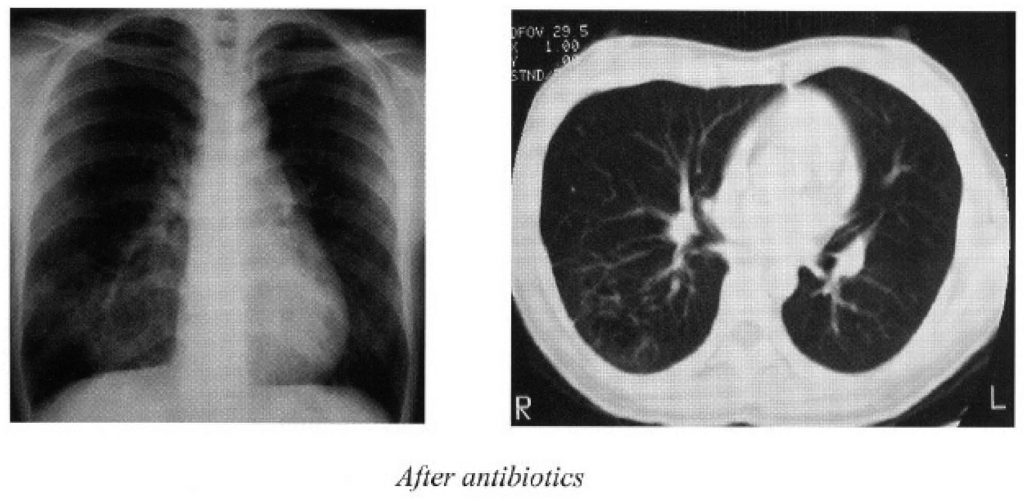

Before the diagnostic serology came back, she was treated with Imipenem/cilastatin 500mg iv q6h for 5 days empirically and was switched to ceftazidime 2g iv q8h when the diagnosis was made. The serology titre dropped four-fold after one week of treatment. However, she developed leucopenia and skin rash. The diagnosis of drug allergy was confirmed with skin biopsy. Ceftazidime was discontinued, and rash subsided. Finally the patient was put on oral doxycycline and TMP-SMZ for maintenance.

The oral medication (doxycycline and TMP-SMZ) was maintained for 6 months. The ensuing CXR showed resolving cavitating pneumonia with residual right lower lobe haziness, see figure. The serial pseudomallei titer remained at 1:40 on subsequent follow up.